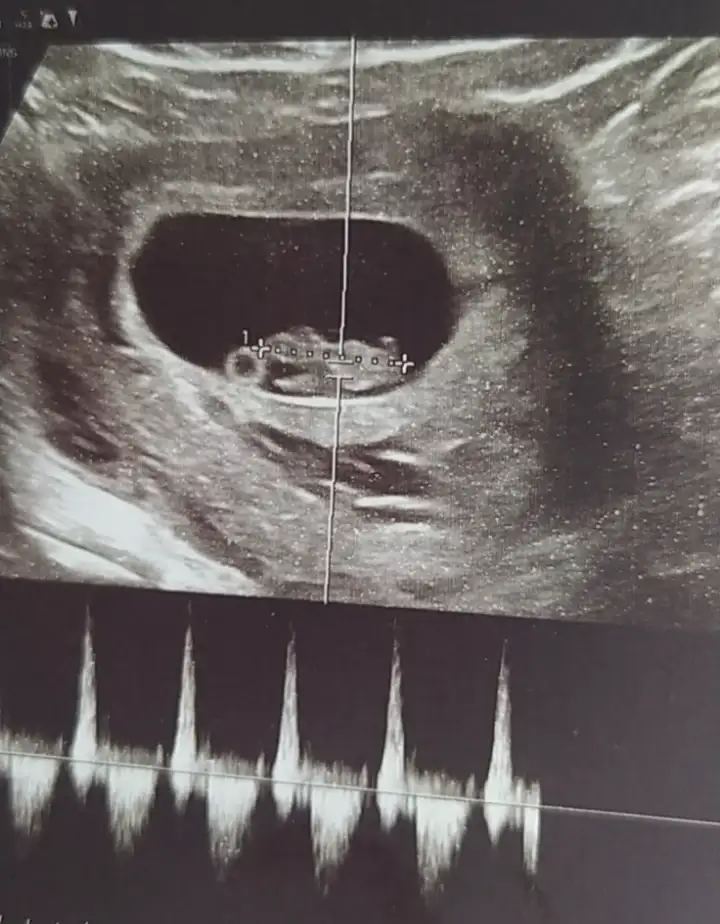

Erkeğe benziyor canımbenim için de bakar mısınız ilki 6 +4 ikinci fotoğraf 8+3 sonuncusu 10+1 Eki Görüntüle 3623528 Eki Görüntüle 3623526 Eki Görüntüle 3623525